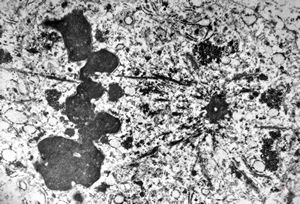

M,59y. | mitosis - angiomatous tumor, Kaposi sarcoma v.s.